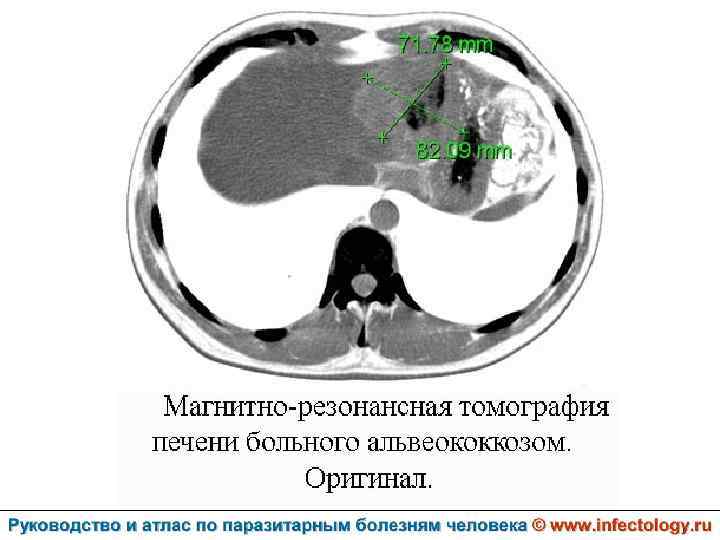

Альвеолярный (многокамерный) эхинококкоз человека (альвеолярный гидатидоз) (шифр по МКБ 10 - B 67. 5 -7) – зоонозный биогельминтоз, характеризующийся чрезвычайно тяжелым хроническим течением, первичным опухолевидным поражением печени, нередко с метастазами в головной мозг и легкие, а также во многие другие органы. Заболевание часто заканчивается летально.